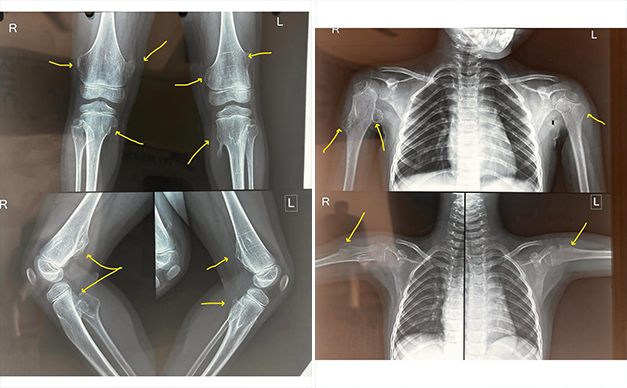

Multiple Hereditary Exostosis (also known as Hereditary Multiple Osteochondromas) is a rare genetic bone disorder characterized by the growth of multiple benign bone tumors, called osteochondromas or exostoses. These growths typically develop near the growth plates of long bones (like the femur, tibia, and humerus) during childhood and adolescence.

🩻 Diagnosis:

- X-rays to visualize exostoses